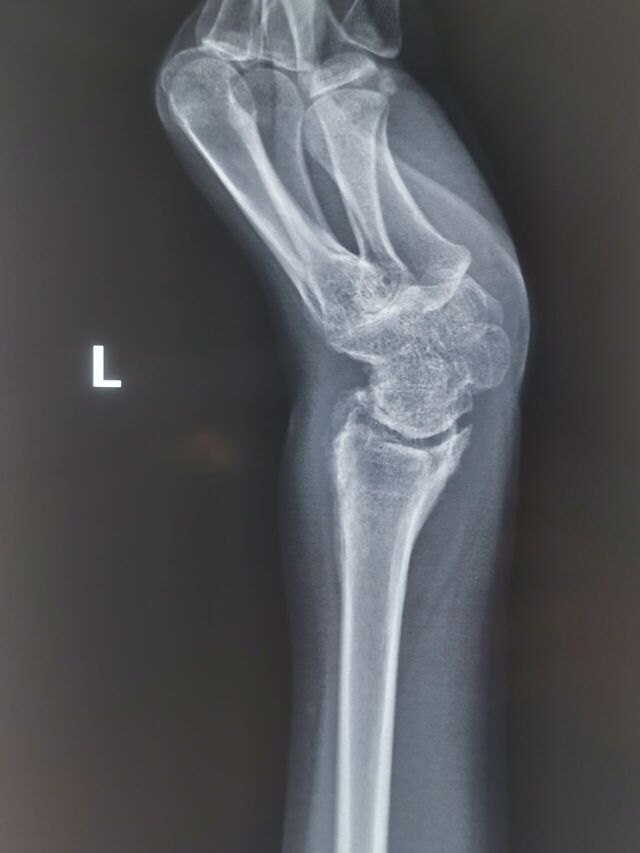

陈旧性月骨周围脱位,创伤性关节炎,下尺桡不稳

IMG_20231025_095800.jpg

IMG_20231025_095755.jpg

IMG_20231025_095748.jpg